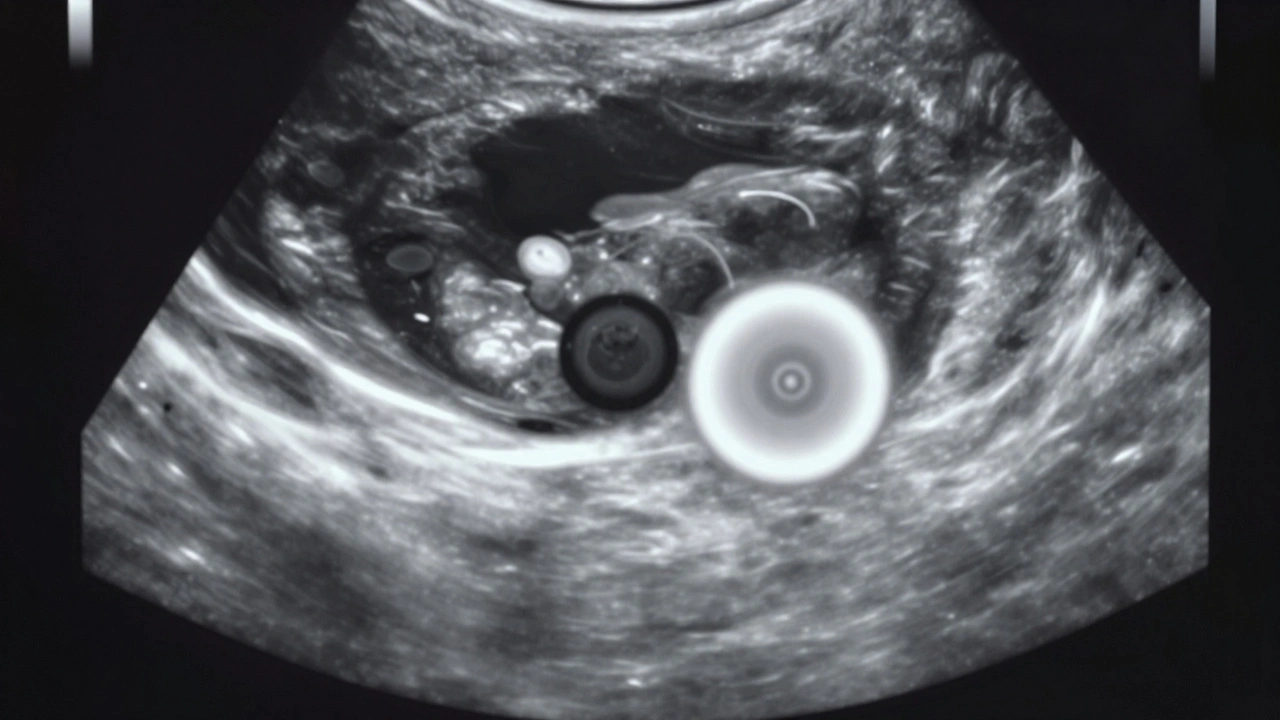

Už v tomto stádiu se často objevuje i žloutkový váček. To je malý, kulatý, často bílý nebo světle šedý kruh vedle gestačního výrůstku. Nejde o plod, ale o strukturu, která v těchto raných dnech vyrábí krevní buňky a poskytuje živiny, dokud se nevytvoří placentu. Žloutkový váček je důležitým ukazatelem, že těhotenství je životaschopné. Pokud ho není vidět, může to znamenat, že je těhotenství ještě příliš rané - nebo že došlo k neúspěšnému početí.

Abstraktní ilustrace raného těhotenství s gestačním výrůstkem a žloutkovým váčkem v mikroskopickém prostředí.